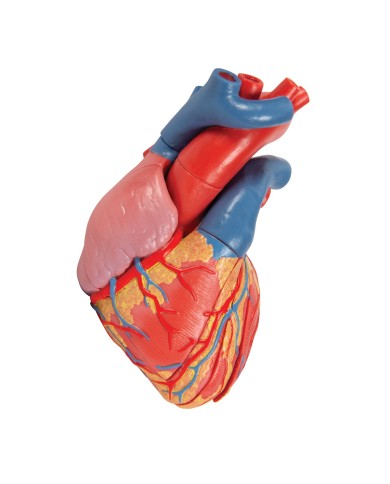

Fra i modelli di base segnaliamo il modello di cuore classico in due parti, in cui le due metà del cuore sono tenute insieme da potenti magneti.

Inoltre nella categoria sono presenti anche i modellini anatomici di cuore con bypass e con sistema di conduzione, fino ai modelli anatomici comparativi di patologie del cuore.

Per una migliore comprensione delle strutture anatomiche del cuore sono stati realizzati anche dei modelli anatomici di cuore ingrandito, si va dai piccoli ingrandimenti fino ai modelli di cuore per la formazione in aula, come il modello anatomico di cuore gigante prodotto da 3B Scientific: un modello di cuore ingrandito di ben otto volte.